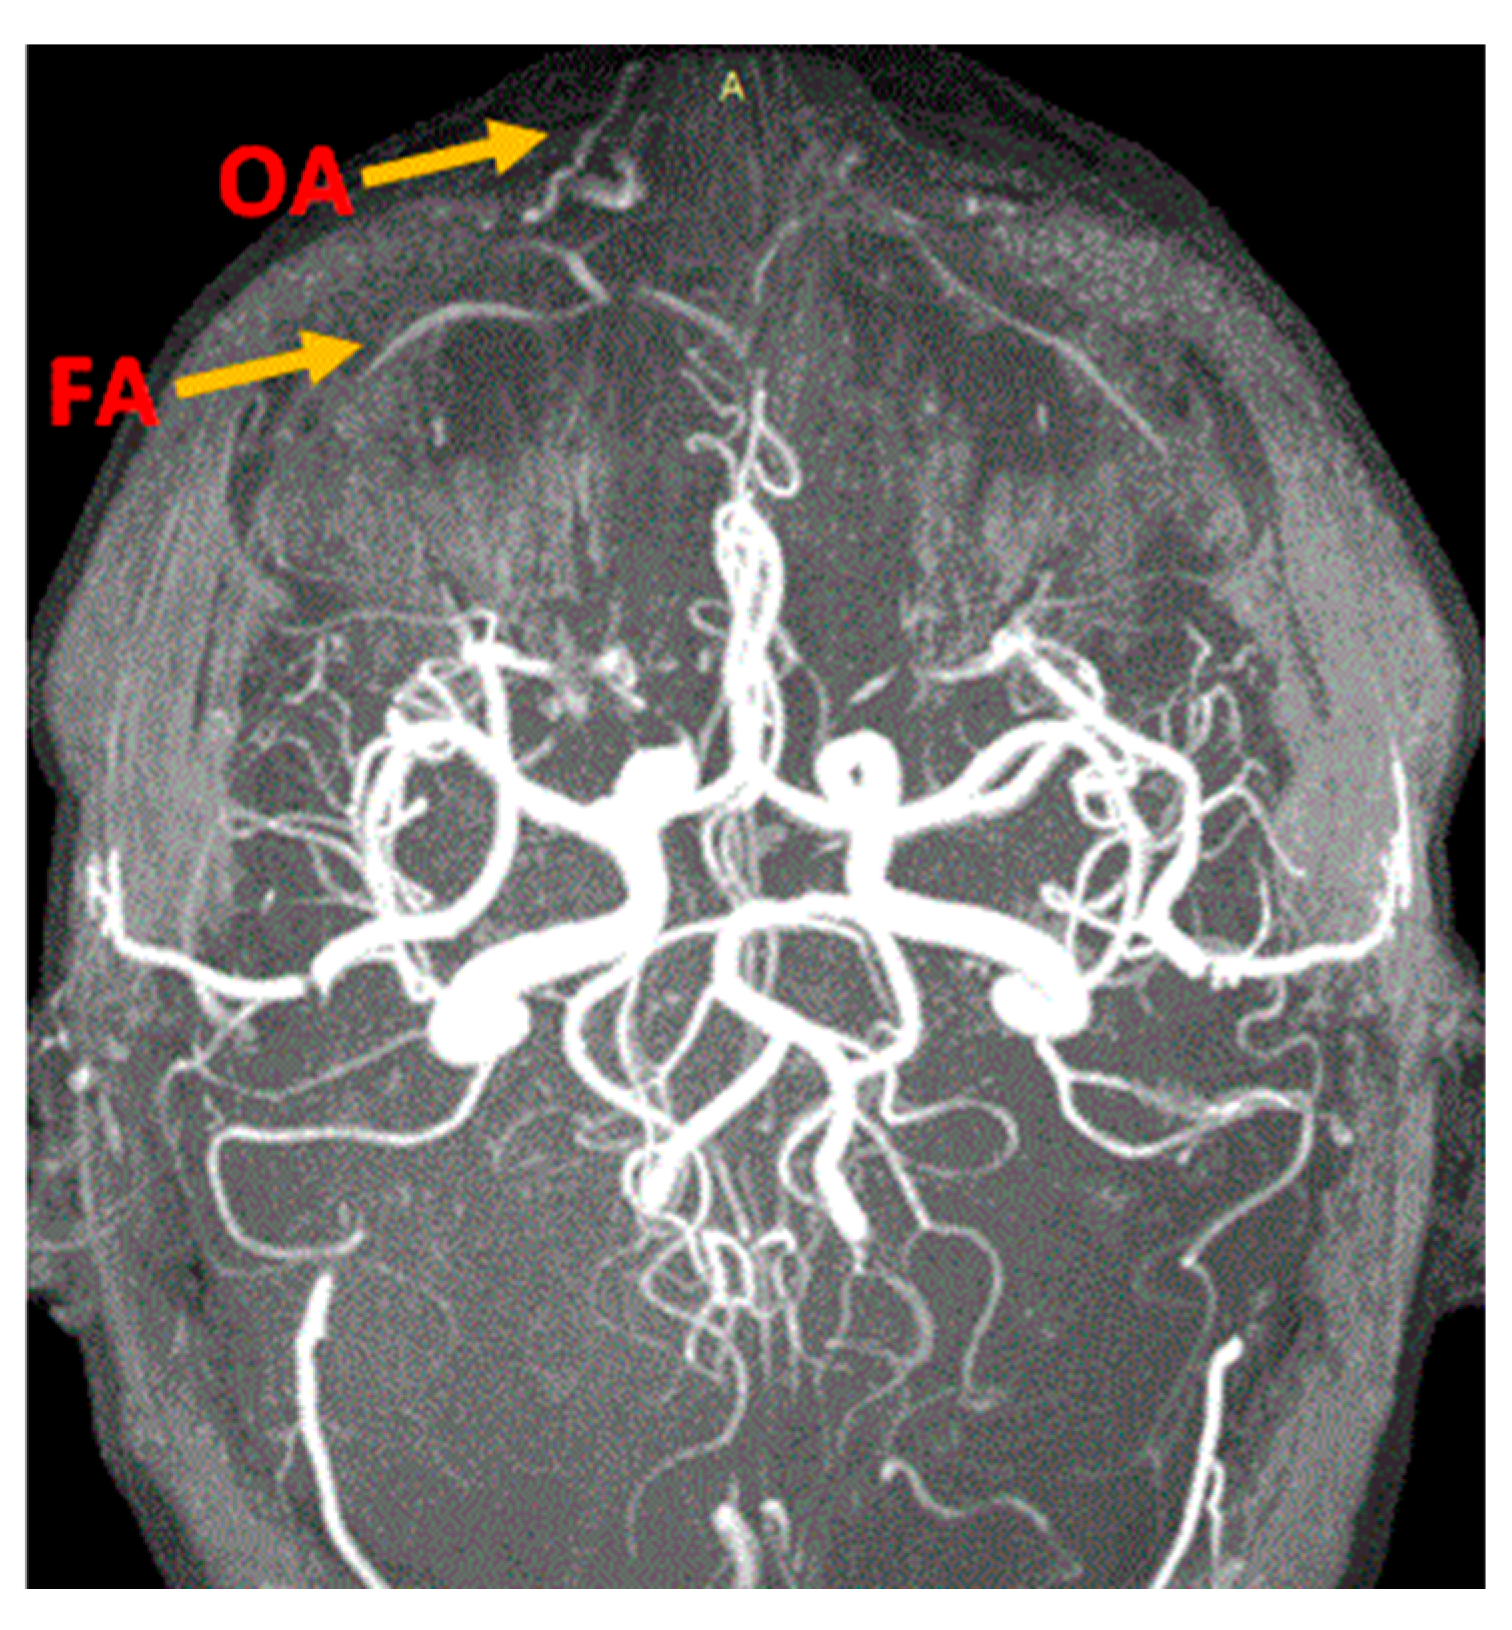

MRA easily illuminated the main blood sources of the nasal region, even if the examination protocol was not dedicated to the exploration of this region. We could identify the branches of the type 1 facial and ophthalmic arteries of the nasal region (Figure 1 and Figure 2) and at least one branch coming from the supraorbital artery (Figure 2).

Figure 1. Branches of facial (FA) and ophthalmic arteries (OA) for the nasal region. MRA VPRV 18 yo healthy patient. 9 min and 13 s time of exposure. A: Artery.